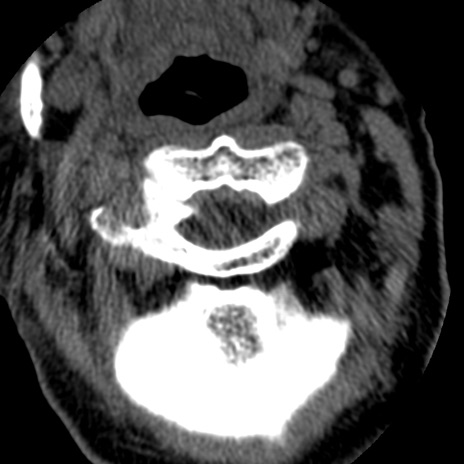

症例50 頚椎CT(横断像)

頚椎CT